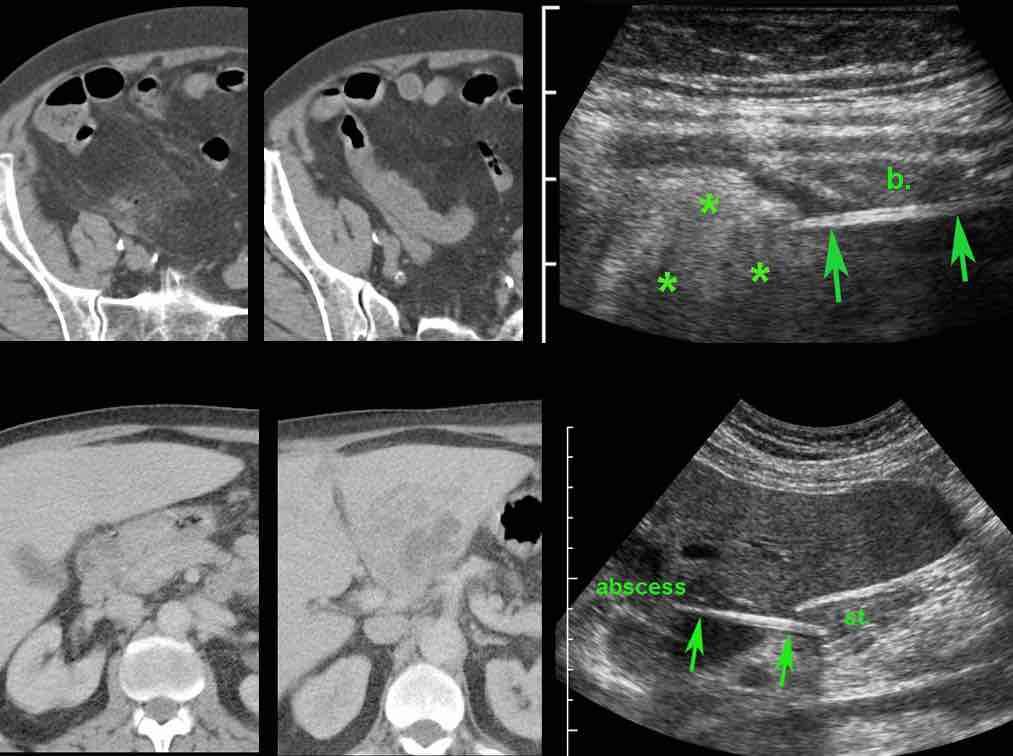

Ở bệnh nhân A, hình ảnh CT cho thấy bóng khí, thâm nhiễm mỡ và dày thành ruột cục bộ, gợi ý thủng cục bộ, nhưng không thấy dị vật.

Siêu âm ngay lập tức vùng này đã phát hiện rõ ràng một dị vật sắc nhọn (mũi tên) xuyên qua thành ruột (b.) vào lớp mỡ xung quanh đang viêm (*).

Ở bệnh nhân B, dày thành hang vị và áp xe gan lân cận gợi ý dị vật gây thủng, tuy nhiên không thể xác định được trên CT.

Siêu âm, được thực hiện với sự hiểu biết về kết quả CT, đã dễ dàng phát hiện dị vật, rõ ràng là đồng tỷ trọng. (st. = dạ dày)